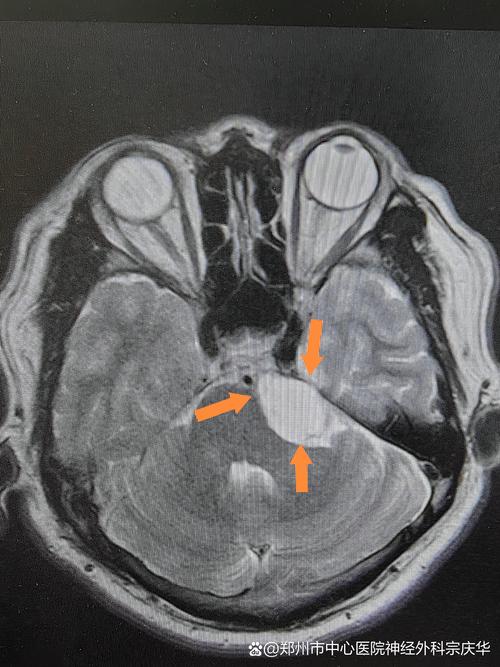

脑肿块是指颅内的占位性病变,包括肿瘤(良性或恶性)、脓肿、血肿、囊肿等,MRI是发现和初步判断脑肿块性质的首选方法。

- 发现和定位:能非常敏感地发现非常微小的肿块,并精确显示其位置、大小、形状以及与周围脑组织(如重要的血管、神经核团)的关系。

- 肿瘤:通常在T2像上呈高信号(白色),在T1像上呈低信号(黑色)。

- 囊肿:在T1和T2像上都呈非常均匀的高信号,像一个“水泡”。

- 增强扫描 (Contrast-Enhanced MRI):这是至关重要的一步,通过静脉注射造影剂(钆剂),可以观察肿块的血供情况。

- “强化”意味着肿块血供丰富,这是恶性肿瘤的典型特征,在图像上,肿块会变得非常亮。

- 不同类型的肿瘤,其强化的方式(均匀强化、环形强化、不均匀强化)也不同,有助于鉴别诊断。